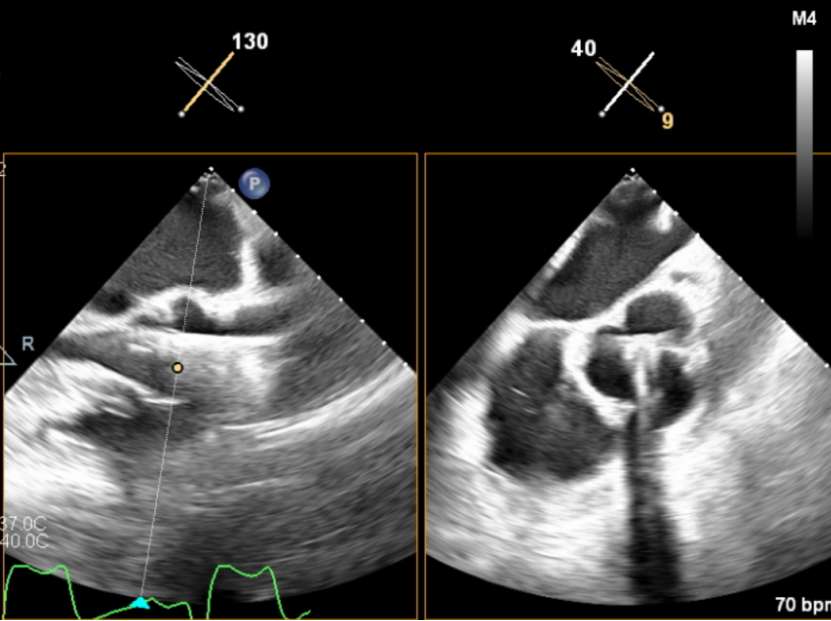

输送器顺利跨瓣,释放外鞘管,开始定位释放,超声评估可见定位件入窦可,后释放内鞘管,打开瓣架,瓣叶活动良好,无瓣周反流,综合考虑瓣膜稳定良好,脱钩释放。

(瓣膜展开)

(瓣膜脱钩)

脱钩后输送器回收,瓣膜无位移及形变,确认瓣膜完全脱钩,回撤输送系统,超声再次评估,瓣膜位置及形态良好,无瓣周漏,峰值流速1.18m/s,平均压3mmHg,患者未诉不适,入路缝合后返回病房。